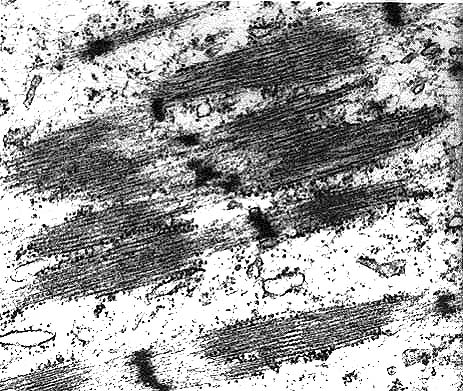

Electron micrograph of neoplastic cells exhibiting several sarcomeres with prominent Z bands and actin filaments.

Contributor's Diagnosis and Comments: Rhabdomyosarcoma. Section of skin contains a densely cellular, multilobular, pleomorphic spindle-cell neoplasm. Groups of neoplastic cells are packeted by a thin encircling rim of fibrous connective tissue. Neoplastic cells are elongate with ample granular cytoplasm and indistinct cytoplasmic borders, large round to oval open-faced nuclei, and a prominent single nucleolus. Mitotic figures are frequent. A few multinucleated neoplastic cells are present; nuclei are occasionally arranged in a linear fashion. Some cells have cytoplasmic cross-striations, which were better illustrated with PTAH staining. Neoplastic cells stained positively for desmin and actin. Sarcomeric structures were visualized by transmission electron microscopy (enclosed photo).

Ultrastructurally, rhabdomyosarcoma cells contain actin filaments (5 nm in width) and myosin filaments (10 nm in width) that form Z-bands, I-bands, and M-bands (see electron micrograph accompanying this case). Additionally, neoplastic cells contain abundant mitochondria and glycogen, and there are indentations of the nuclear membrane.